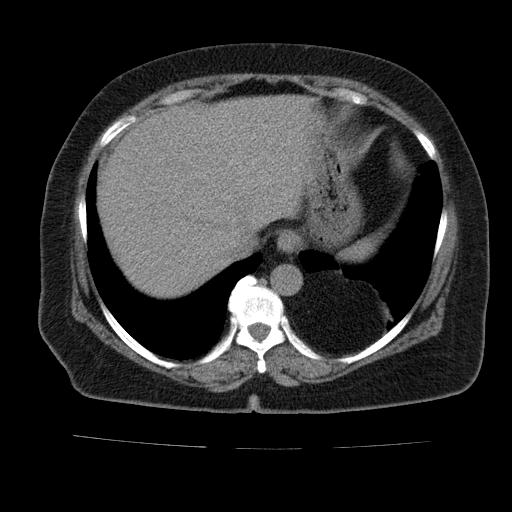

Анатомия диафрагмы и треугольника Бохдалека

Раздел: Визуальный дайджест